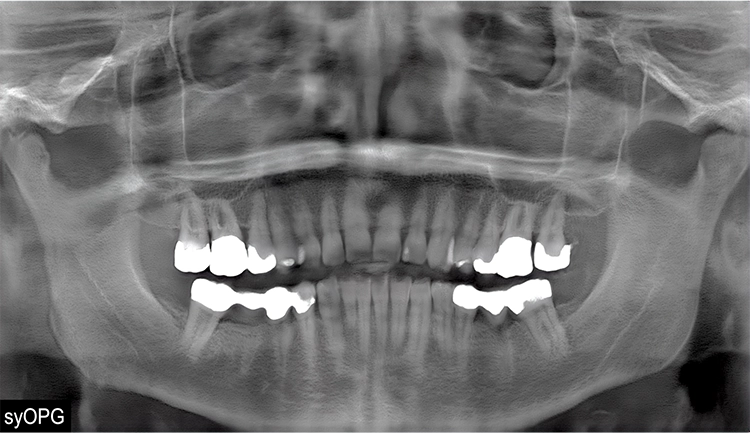

In einem umfangreichen, randomisierten, verblindeten Fragebogen wurden 54 approbierte (Zahn-)Ärzt/-innen und 33 Zahnmedizinstudierende gebeten, die Authentizität der Bilder zu prüfen, indem sie die o.g. 45 Bilder entweder als real oder synthetisch bewerteten (Abb. 1 und 2). Zusätzlich wurde ein Einzel-syOPG hinsichtlich spezifischer, diagnostischer Kriterien befundet (Abb. 3). Ferner wurde nach der Selbsteinschätzung sowie der Einschätzung der Bedeutung von synthetischen radiologischen Bildern für den Beruf gefragt. Ein Follow-up-Test zur Überprüfung der Reliabilität wurde ebenfalls durchgeführt.

Die Sensitivität für die Erkennung von syOPGs lag bei 78,2%, die Spezifität bei 82,5%. Die Bildqualität für das Einzel-syOPG wurde mit 6 (Likert-Skala) bewertet und 6 von 11 diagnostischen Kriterien erreichten eine Übereinstimmung. Die Bedeutung für den Beruf wurde im Median mit 7 (Likert-Skala) bewertet. Die im Follow-up gemessene Retest-Reliabilität erbrachte, gemessen mit Cohen‘s Kappa, einen Wert von 0,23, was bedeutet, dass viele Bilder im Follow-up anders als initial bewertet wurden.